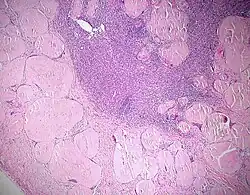

- Käsige Nekrose - Bsp.: Tbc (Epitheloidzelliges Granulom mit Langhans-Riesenzellen und zentraler käsiger Nekrose)